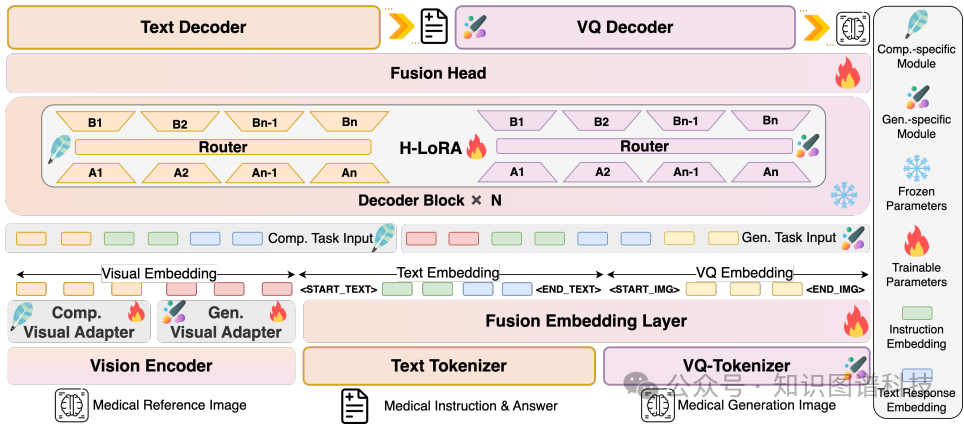

HealthGPT架构:HealthGPT通过离散令牌表示同时覆盖文本和视觉输出,将视觉理解和生成任务统一为自回归任务。其架构结合了分层视觉感知(HVP)和异构低秩适应(H-LoRA)技术。

分层视觉感知(HVP):HVP将图像压缩为多个层次上的离散视觉令牌。具体来说,图像通过多层ViT块转换为一系列特征,这些特征被分为具体粒度和抽象粒度两类。具体粒度特征适用于生成任务,而抽象粒度特征适用于理解任务。

异构低秩适应(H-LoRA):H-LoRA通过低秩矩阵分解将理解和生成任务的异构知识存储在独立的模块中,并通过硬路由选择动态提取任务相关的知识。H-LoRA的计算开销较低,特别适用于大规模任务。

模型选择:选择了CLIP-L/14作为视觉编码器,并使用其第二层和倒数第二层的隐藏状态作为具体粒度和抽象粒度特征。基础模型选择了phi-3-mini和phi-4。

训练阶段:采用三阶段学习策略:

第一阶段

:多模态对齐,分别训练医学理解任务和生成任务的视觉适配器和H-LoRA子模块。

第二阶段

:异构H-LoRA插件适应,微调词嵌入层和输出头,保持H-LoRA子模块冻结。

第三阶段

:视觉指令微调,引入额外的任务特定数据进一步优化模型。

分层视觉感知(HVP)技术通过将图像压缩为多个层次上的离散视觉令牌来设计。具体来说,图像通过多层ViT(Vision Transformer)块转换为一系列特征,这些特征被分为具体粒度和抽象粒度两类。具体粒度特征适用于生成任务,因为它们包含了更多的全局信息;而抽象粒度特征适用于理解任务,因为它们更接近文本空间,包含了更多的语义信息。通过这种方式,HVP能够在不同任务之间灵活地调整视觉输入的粒度,从而提高模型在理解和生成任务中的效率。

异构低秩适应(H-LoRA)技术通过低秩矩阵分解将理解和生成任务的异构知识存储在独立的模块中。具体实现过程中,H-LoRA将 bypass weight matrix分解为两个低秩矩阵,从而减少可学习参数的数量。H-LoRA的优势在于其较低的计算开销,特别适用于大规模任务。与混合专家(MoE)方法相比,H-LoRA通过矩阵合并和路由权重分配机制避免了多重矩阵乘法的延迟,显著提高了计算效率。

HealthGPT采用了三阶段学习策略,具体目标如下:

:多模态对齐。在这个阶段,分别训练医学理解任务和生成任务的视觉适配器和H-LoRA子模块。通过使用高质量的图像-文本对,确保视觉嵌入与文本嵌入的对齐,从而建立初始的模型输出与视觉输入之间的对齐关系。

:异构H-LoRA插件适应。在这个阶段,微调词嵌入层和输出头,同时保持H-LoRA子模块冻结。通过少量的混合数据,确保不同任务的H-LoRA插件能够无缝衔接,形成统一的基础模型。

:视觉指令微调。在这个阶段,引入额外的任务特定数据进一步优化模型,使其能够适应具体的下游任务,如医学视觉理解(如医疗问答、医疗对话和报告生成)或生成任务(如超分辨率、去噪和模态转换)。